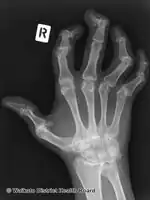

Pain, swelling, or stiffness in one or more joints is commonly present in psoriatic arthritis.[3] Psoriatic arthritis is inflammatory, and affected joints are generally red or warm to the touch.[3] Asymmetrical oligoarthritis, defined as inflammation affecting two to four joints during the first six months of disease, is present in 70% of cases. However, in 15% of cases, the arthritis is symmetrical. The joints of the hand that is involved in psoriasis are the proximal interphalangeal (PIP), the distal interphalangeal (DIP), the metacarpophalangeal (MCP), and the wrist. Involvement of the distal interphalangeal joints (DIP) is a characteristic feature and is present in 15% of cases.

Along with the above-noted pain and inflammation, there is extreme exhaustion that does not go away with adequate rest. The exhaustion may last for days or weeks without abatement. Psoriatic arthritis may remain mild or may progress to more destructive joint disease. Periods of active disease, or flares, will typically alternate with periods of remission. In severe forms, psoriatic arthritis may progress to arthritis mutilans[5] which on X-ray gives a "pencil-in-cup" appearance.[1]

There is no definitive test to diagnose psoriatic arthritis. Symptoms of psoriatic arthritis may closely resemble other diseases, including rheumatoid arthritis. A rheumatologist (a physician specializing in autoimmune diseases) may use physical examinations, health history, blood tests and x-rays to accurately diagnose psoriatic arthritis.

• Radiologic images demonstrating degenerative joint changes.